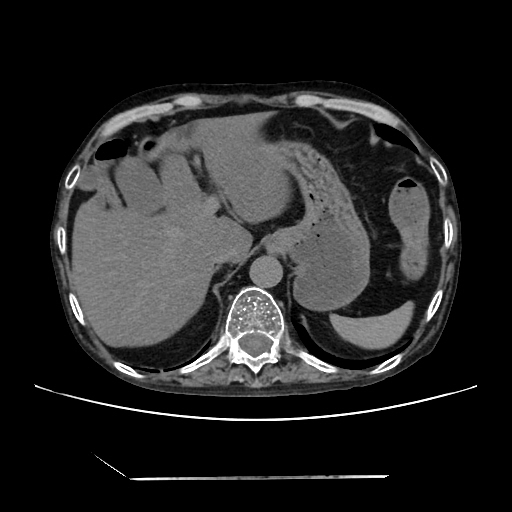

HRCT done on 17Mar16